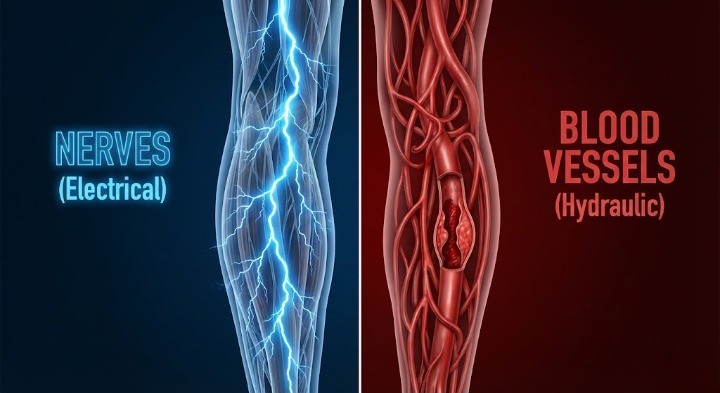

신경 문제 vs 혈관 문제(혈액순환), 어떻게 다를까?

많은 분들이 다리가 저리면 혈액순환이 안 돼서 그렇다며 혈액순환 개선제를 드시곤 합니다. 하지만 의학적으로 신경 눌림과 혈관 막힘은 증상이 미묘하게 다릅니다.

말초동맥질환(PAD)으로 인해 다리 혈관이 좁아지면, 근육에 산소 공급이 부족해져 저림보다는 통증과 경련이 주가 됩니다.